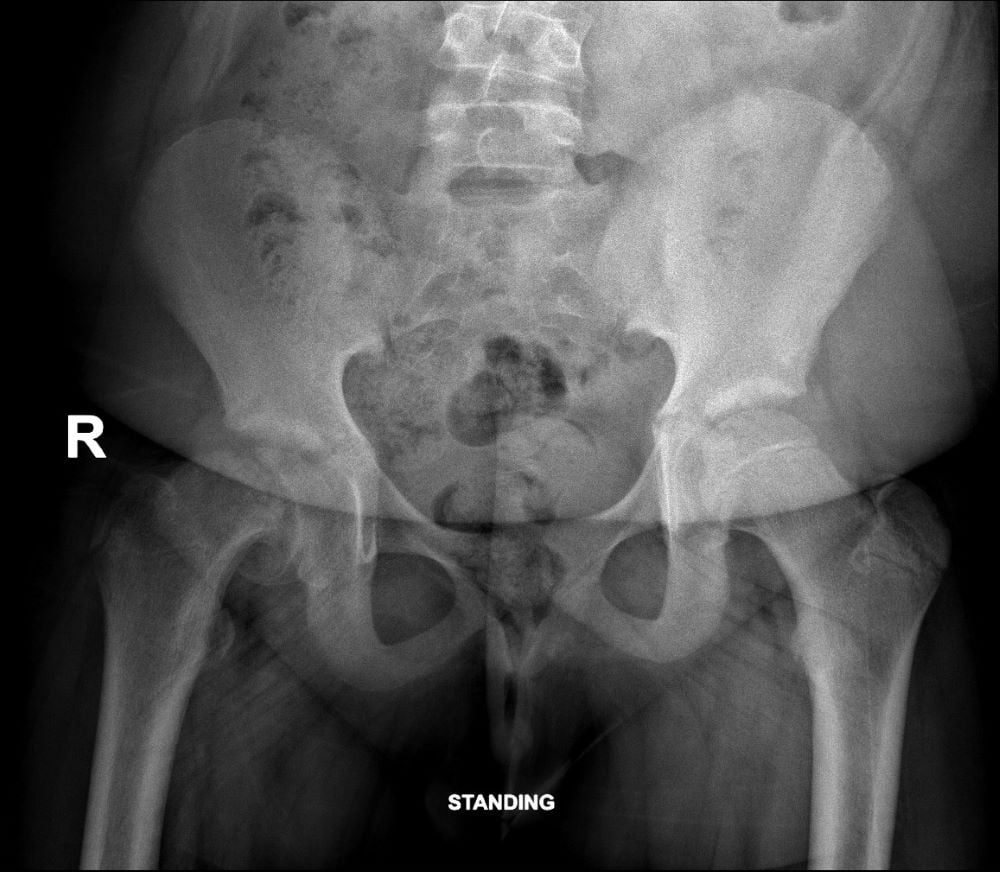

Widening of the growth plate (physis) with blurring and irregularity of the femoral neck (metaphysis). Inferior offset of the head in relation to the neck (early slip).

โMelting ice cream signโ: Femoral head (epiphysis) slipping off the femoral neck (metaphysis) though the growth plate (physis) like an ice cream melting from the cone.

He says, the recommended imaging is an anterior-posterior pelvic view which shows malalignment and widening of the growth plate and a frog-leg lateral view, the most sensitive for detecting early or subtle slips.

โKey radiological signs,โ says Dr Greyling, are:

- Widening of the growth plate.

- Loss of height of the femoral head.

- Loss of alignment of the anatomical lines that intersect with the femoral head.

- โMelting ice cream signโ slipping off the femoral neck at the growth plate (epiphysis).